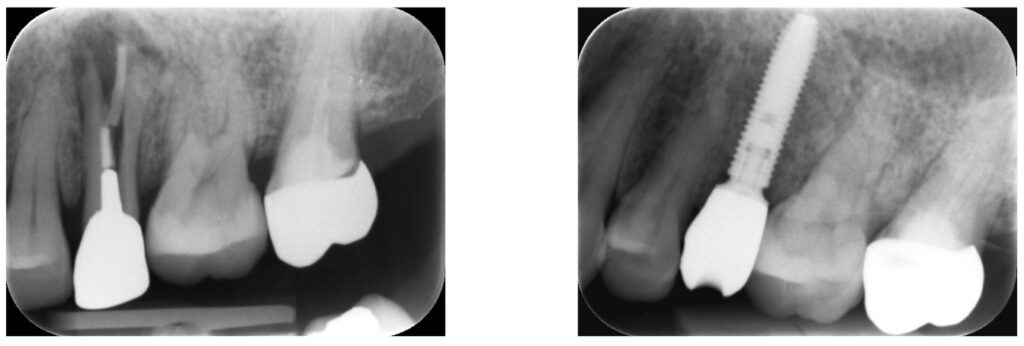

症例42:歯根破折した歯を抜歯し、インプラント治療

左側の顔が腫れた。噛んだら痛い。

歯根破折した歯を抜歯し、同時にインプラント治療する

しっかり噛める咬合関係の確立。